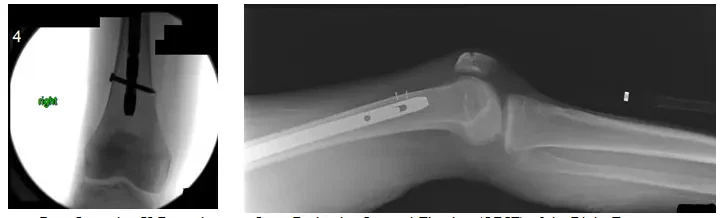

Les radiographies postopératoires montrent une fixation interne à réduction ouverte (ORIF) du fémur droit.

Les radiographies montrent une tige intramédullaire s’étendant du grand trochanter, à travers la fracture fémorale proximale, jusqu’à la tige distale du fémur où il y a une vis horizontale.